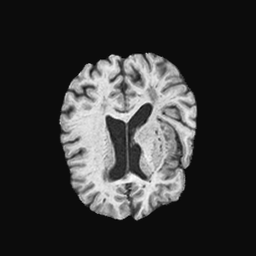

Exp. 1: Segmented adult brain data is used to evaluate our network’s regression performance with known ground truth . 85 brains from the ADNI data set[1] were randomly selected; 70 brains for and 15 brains for . Fig. 2 shows an example slice of the ground truth and the reconstructed .

Reconstructing from initialisation without SVR yields a PSNR of 23.7 1.09; with subsequent SVR the PSNR increases to 29.52.43 when tested on 15 randomly selected test volumes after four iterations of SVR.

Here we show for Exp. 1, Exp. 2, and Exp. 3 randomly selected examples of images that have been presented to the network (ground truth) compared to an image sampled at the predicted location.

In these experiments, we present a ground truth (GT) image to the network to estimate the respective transformation parameters needed to reorient the slice in its correct world co-ordinates. Using the transformation parameters, we generated a slice from the 3D atlas in the location where the network has predicted that slice should be (denoted as SVRNet).

The slices are compared side-by-side to give a visual representation of “where the slice really is” and “where the network thinks the slice is”.

0..5.1 Exp. 1:

Slices, extracted from a correctly registered and reconstructed 3D volume, from the testing data set are presented to the network. The predicted slice is extracted from the same volume, using parameters estimated by SVRNet as shown in Fig. 8 and 9.